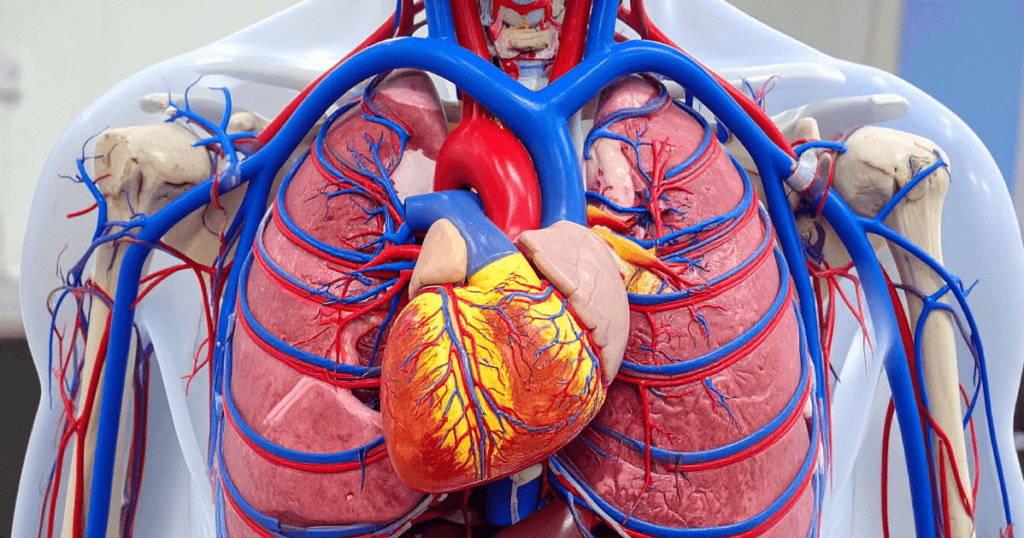

By combining high-resolution CT technology with an intravenous contrast agent, CTCA produces detailed 3D images of the heart vessels, allowing precise evaluation of blockages, vessel narrowing, plaque burden, and calcium deposits-often before symptoms become severe.

Cardiac CT imaging allows clinicians to assess vessel anatomy, plaque characteristics, and overall cardiac structure in a single examination.